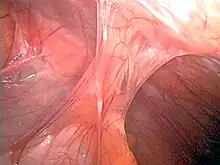

Adhesions formed following appendectomy

Adhesions are fibrous bands that form between tissues and organs,[1] often as a result of injury during surgery. They may be thought of as internal scar tissue that connects tissues not normally connected.